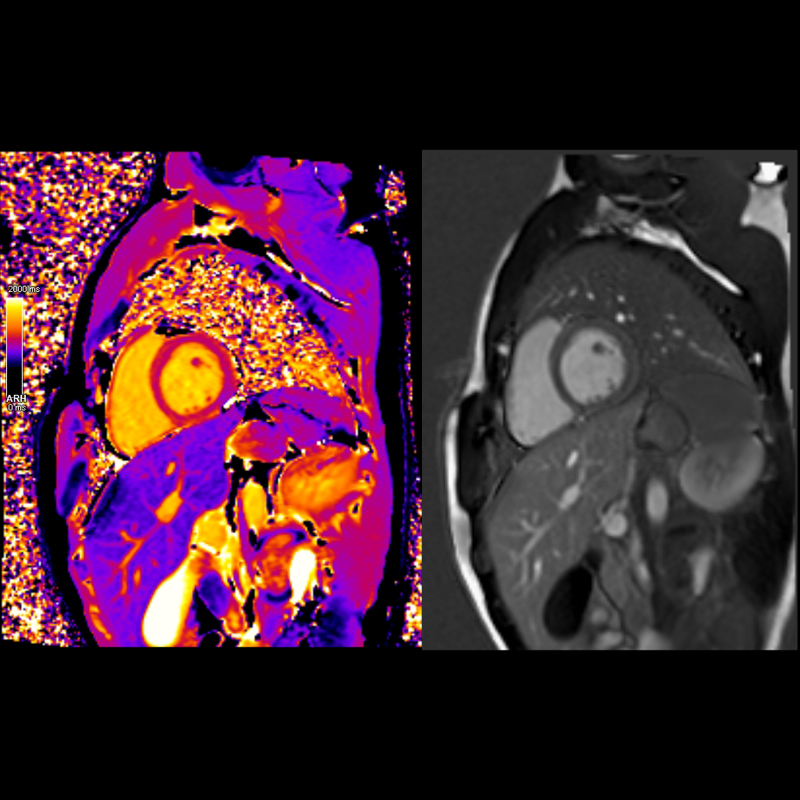

Kardiyolojik değerlendirmelerde detaylı kalp yapıları ve akım ölçümleri sağlar.

o Kardiyolojik değerlendirmelerde detaylı kalp yapıları ve akım ölçümleri sağlar.